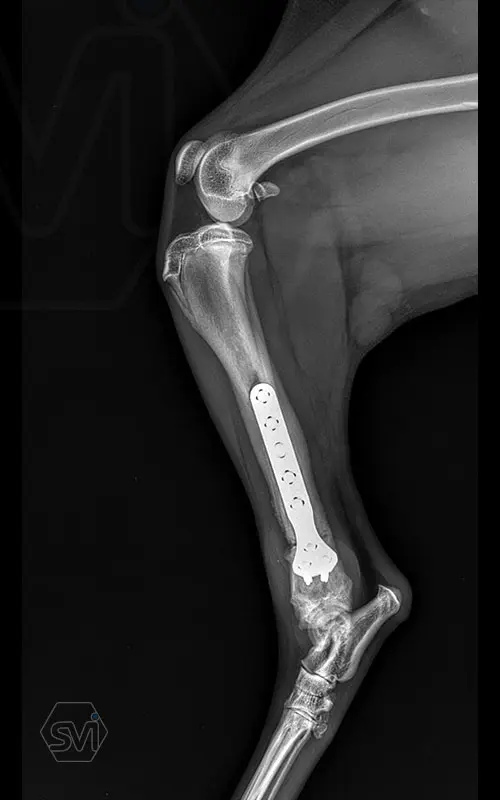

Multifunctional symmetrical long polyaxial locking plate - designed for the treatment of fractures close to joints

A special member of the polyaxial locking plate family is the multifunctional long plate, which is an extended version of the well-known symmetrical TPLO plate, with a 5-3 hole distribution. The plate also received a DCP hole to be able to create compression, and there is a mini-hole on the head end to facilitate the placement of the temporarily used K-nail. The burrs on the side facing the bone surface are intended to reduce the contact surface between the plate and the bone (limited contact).

The plate is a member of the large polyaxial locking family, suitable for 2.7-3.5-4.0 mm screws. We recommend it for fixaton of fractures close to joints, wedge osteotomies with axis correction (closing and opening), or for CWTO operations.